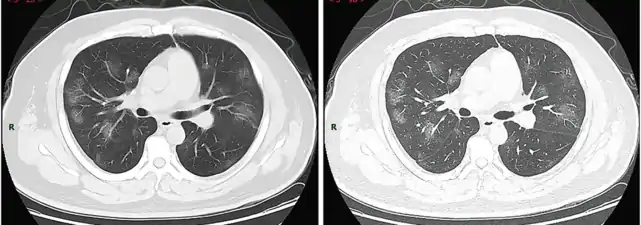

* 14. april 2020 : (PDF-fil) "Information om PCR test for COVID-19 til almen praksis" Arkiveret 18. april 2020 hos Wayback Machine - Billedbeskrivelse på Commons : "Typical CT imaging manifestation (case 1). A 38 years old male with fever without obvious inducement (39.3 ℃), dry cough and shortness of breath for 3 days. Laboratory test: normal white blood cells (6.35 × 109/L), decreased lymphocytes percentage (4.1%), decreased lymphocytes count (0.31 × 109/L), decreased eosinophil count (0 × 109/L)), increased C-reaction protein (170.91 mg/L), increased procalcitonin (0.45 ng/ml). Imaging examination: multiple patches, grid-like lobule and thickening of interlobular septa, typical "paving stone–like" signs. a SL(Slice): 6 mm; b high-resolution computed tomography(HRCT). HRCT. high-resolution computed tomography"